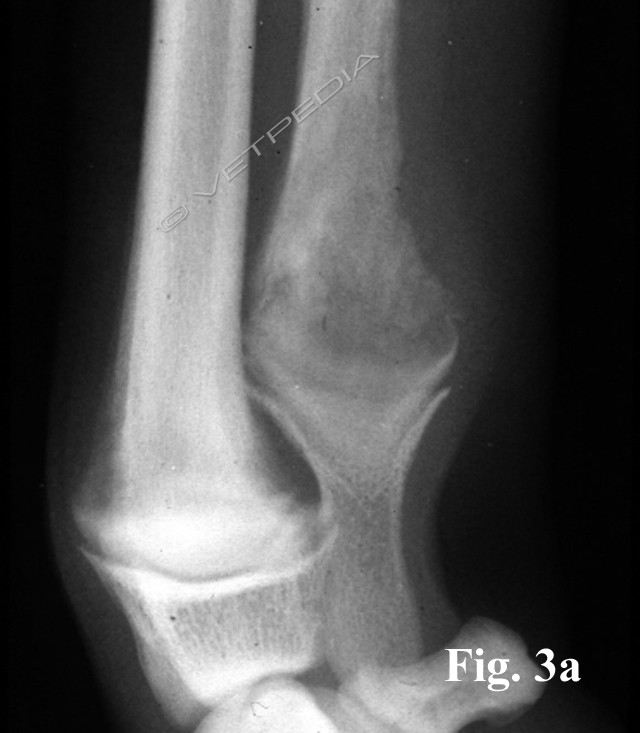

L’esame radiografico di norma si può eseguire senza sedazione; si può eventualmente eseguire una breve anestesia gassosa con induzione diretta. Viste le dimensioni della cavia, conviene eseguire di routine le proiezioni laterale e ventrodorsale di tutto il corpo, a meno che l’animale non sia gravemente debilitato e manovre stressanti poss...